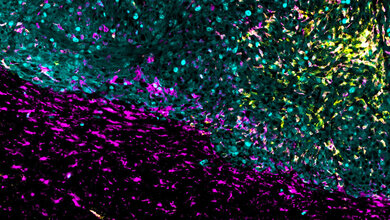

Die Idee von Dr. Dr. Venkataramani war es, ein Virus gegen die Tumorzellen ins Feld zu führen, das auf die Infektion von Nervensystemen spezialisiert ist: Tollwutviren werden meist über den Biss eines infizierten Tieres übertragen und befallen Nervenzellen. Von der Bisswunde wandern sie entlang der Nervenverbindungen bis ins Gehirn, wo sie eine lebensbedrohliche Entzündung hervorrufen. „Die Fähigkeit der Tollwutviren, von einer Nervenzelle über deren Kontaktstellen auf die nächste Nervenzelle überzuspringen, haben wir uns zunutze gemacht“, sagt der Neurologe. Veränderungen am Viruserbgut sorgten dafür, dass die Viren von der Tumorzelle nur auf direkt verbundene Nervenzellen überspringen. Eine Übertragung von diesen auf weitere Nervenzellen ist nicht möglich. Darüber hinaus überträgt das veränderte Virus die genetische Bauanleitung für Proteine, die fluoreszieren und dadurch sowohl Tumorzellen als auch deren direkte Kontaktpartner sichtbar machen. „Mit bisherigen Techniken ließen sich diese Zell-Zell-Kontakte nur in unmittelbarer Nähe des Tumors nachvollziehen. Mit Hilfe der Tollwutviren sehen wir erstmals auch die Kontaktpartner, die über lange Zellausläufer über weitere Strecken mit den Tumorzellen Verbindung aufnehmen“, sagt Svenja Tetzlaff aus dem Team von Dr. Dr. Venkataramani, eine der beiden Erstautorinnen des Artikels. „Wir können nun das gesamte Netzwerk der Tumor-Nerven-Verbindungen im Gehirn kartieren.“

Die molekulare Kontaktnachverfolgung hat ergeben, dass die Tumorzellen sich extrem schnell mit den Nervenzellen vernetzen. Lange bevor der Tumor mittels klinischer Bildgebung sichtbar werde und lange bevor es zu neurologischen Störungen komme, seien die Krebszellen bereits an die neuronalen Netzwerke angebunden. „Damit haben wir nicht gerechnet. Es bedeutet, dass das aggressive Wachstum dieser Hirntumoren bereits in einem sehr frühen Stadium, lange vor den ersten Krankheitsanzeichen stattfindet“, so Ekin Reyhan, Nachwuchswissenschaftlerin an der Medizinischen Fakultät Heidelberg und ebenfalls Erstautorin der Arbeit. Zudem offenbarte der nun mögliche Blick auf weiter entfernte Kontaktpartner erstmals mehrere verschiedene Nervenzelltypen. Eine besondere Rolle scheinen jedoch sogenannte acetylcholinerge Nervenzellen zu spielen, die für Gedächtnis- und Aufmerksamkeitsprozesse wichtig sind. Wurden die Tumorzellen genetisch gezielt so verändert, dass sie von diesen Nervenzellen keine Signale mehr empfangen konnten, verlangsamte sich das Tumorwachstum im Tierversuch.